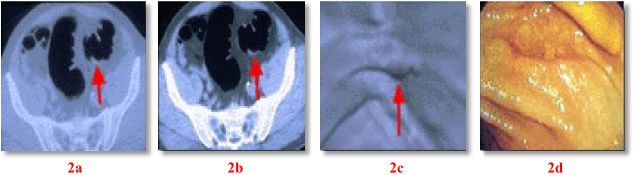

Research has shown that Virtual Colonoscopy is better able to see polyps than Barium Enema and is nearly as accurate as Conventional Colonoscopy. Fig. 1 shows a polyp and Fig. 2 a flat cancer seen on 3 techniques: 2D axial CT (Fig. 1a, 2a-b), 4D VC (Fig. 1b, 2c), and conventional colonoscopy (Fig. 1c, 2d). Most patients report that the Virtual Colonoscopy technique is more comfortable than either Barium Enema or Conventional Colonoscopy. Studies suggest a very high sensitivity and specificity (96%) for the detection of polyps 1 cm or greater. Such polyps have significant malignant potential. Sensitivity for polyps less than 1 cm is significantly less. Although controversy exists as to the definition of a "significant" polyp with regard to size, polyps < 1 cm in size have a low probability of malignancy and the likelihood of any single lesion progressing to cancer is also small.

VC may become a screening tool for detecting colorectal neoplasia, potentially supplanting Conventional Colonoscopy as a tool for detecting lesions. Increased screening, with increased detection, should decrease the incidence of colorectal cancer, as premalignant growths can be found at an earlier stage. About 5% of colon cancers (flat cancers) arise from normal mucosa and not from polyps and are difficult to identify on conventional and virtual colonoscopy, while axial helical CT images improve detection of such cancers.